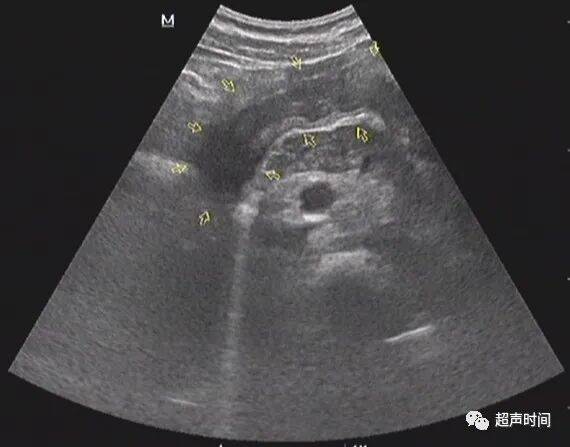

图 3 胃窦纵切:胃窦壁不规则增厚,回声减低,僵直不蠕动

图 4 胃窦横切呈「假肾征」,提示胃壁异常增厚

胃窦壁不规则增厚,回声减低, CDFI :其内可见高阻血流。胃窦壁僵直,探头按压长时间不蠕动。余胃壁蠕动良好。

超声提示:胃窦病变,考虑胃窦癌(建议胃镜活检及增强 CT 检查)

如果观察到胃壁增厚(厚度达到 10 mm )回声减低、内高阻血流、僵直不蠕动,发现其中任意一项,就可以提示胃异常病变,建议胃镜检查。